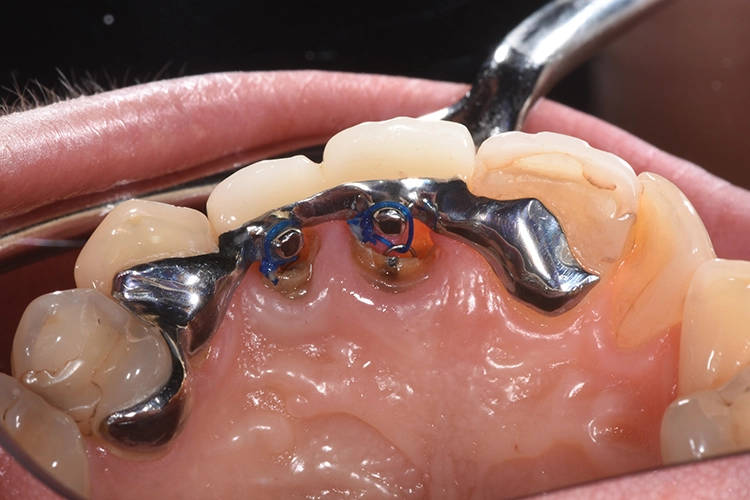

Fall 2: KFO-Extrusion

Ihr wurden die verschiedenen Behandlungsmöglichkeiten erklärt. Die Patientin wünschte sich den Erhalt der eigenen Zähne. Aufgrund der Breite der Lücke und schwierig zu schienender Situation entschieden wir uns für eine kieferorthopädische Extrusion der beiden Wurzelreste.

Dr. Blume